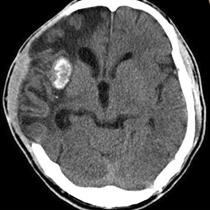

囊虫的钙化形态各异,取决于脑囊虫四个主要阶段(也称为Escobar的病理阶段):a囊泡期:活的寄生虫有完整的包囊膜,囊壁光滑,内可见头节,无强化。因此没有宿主反应。b胶状囊泡期:包囊破溃,包囊的液体渗入组织,周围有水肿。此期引发强烈的免疫反应,所以此期的临床反应最重。见下图。

c颗粒结节期:随着囊肿进一步变性缩小,水肿减轻;增强仍存在。d结节钙化期:终末期,静止的钙化囊残余;没有水肿。